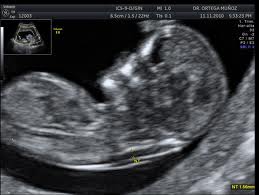

Ecografía. La ecografía es el método de exploración imprescindible en el ámbito del diagnóstico prenatal. Tiene unos momentos clave de aplicación:

En el primer trimestre. Nos permite detectar algunas imágenes consideradas "marcadores de cromosomopatías". La más válida y aceptada en los últimos años es la conocida como “translucencia nucal”, estructura visualizable en el dorso del feto entre la semana 11 y 14. Si supera ciertas dimensiones (3 mm.), deberíamos ofrecer la realización de prueba invasiva. Igualmente importante es visualizar el hueso nasal, pues su ausencia se ha relacionado con el Síndrome de Down.

En el segundo trimestre. Especialmente alrededor de la semana 20, es la época más adecuada para el diagnóstico de la mayoría de malformaciones de tipo anatómico. Debe practicarse por personal especialmente cualificado, preparado y acreditado para este tipo de ecografías. Igualmente se requieren equipos eccográficos de alta definición, dotados de tecnología como el Doppler Color y la Tridimensión, que nos permiten descubrir detalles muy precisos de toda la anatomía fetal.